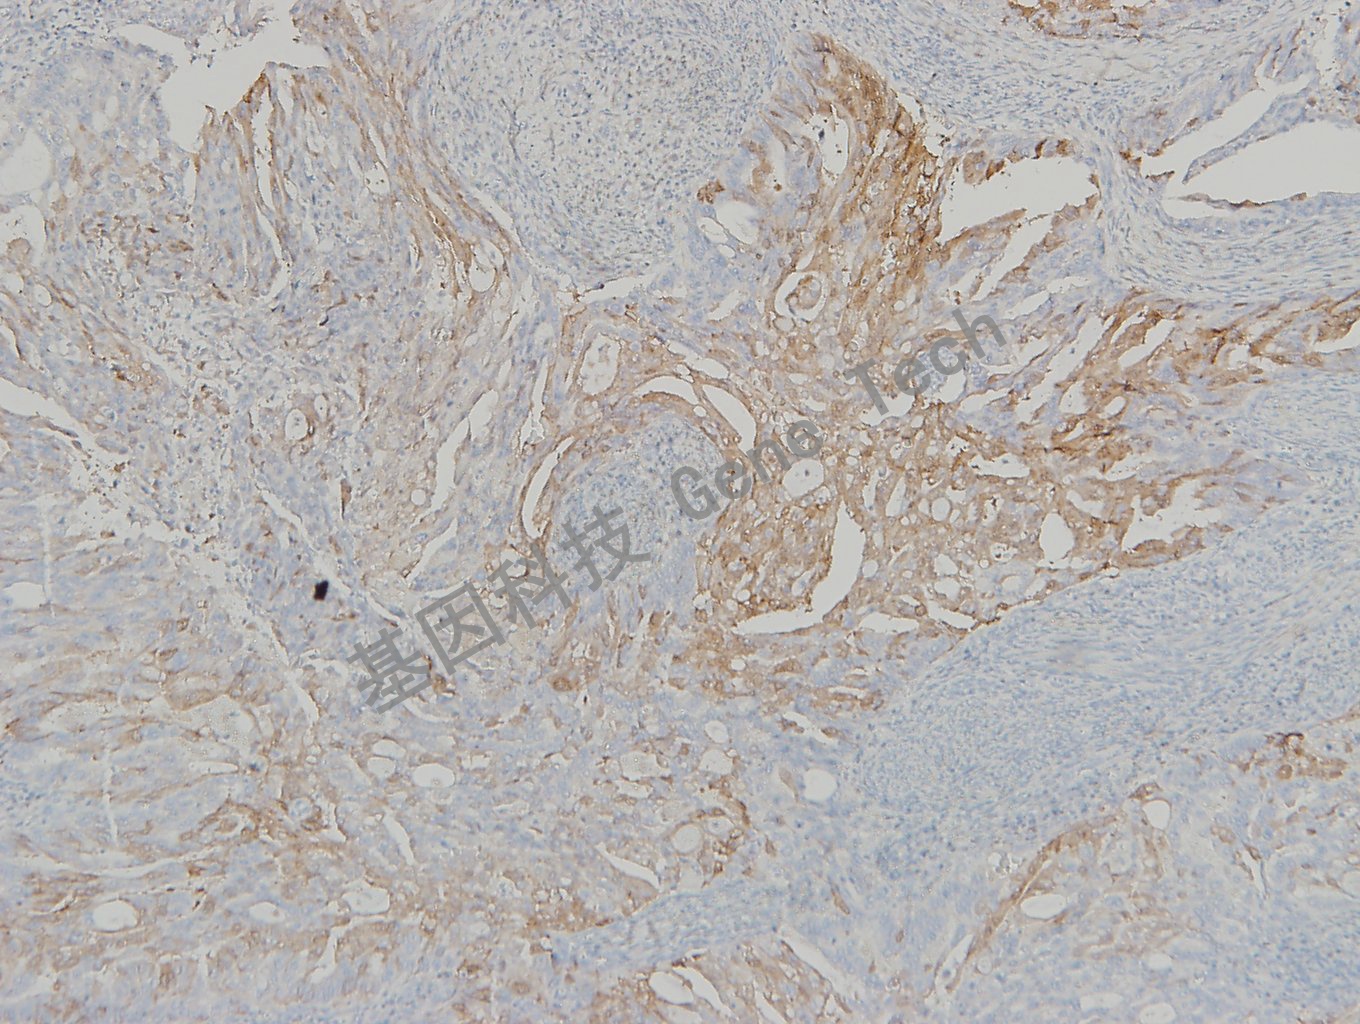

宫颈癌石蜡切片,用 p16(GT2330)染色,细胞浆/细胞核阳性,DAB 显色。